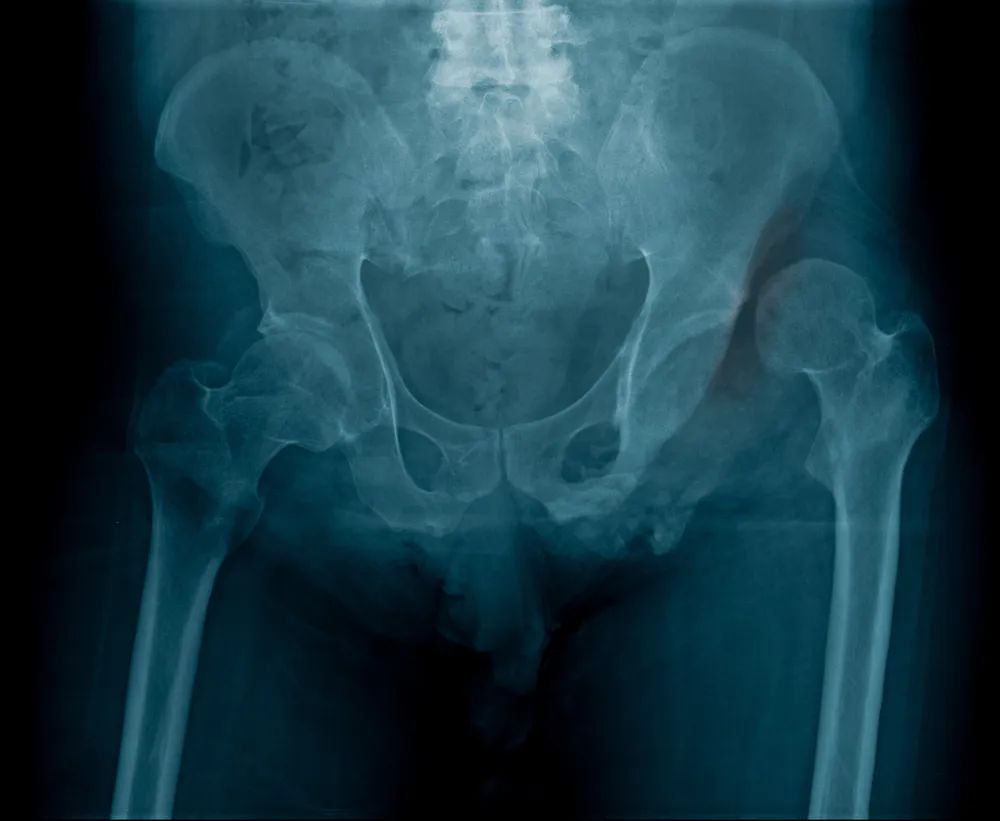

1、诊断:可以通过 X 线明确脱位类型,CT 平扫可以评估合并损伤的情况。